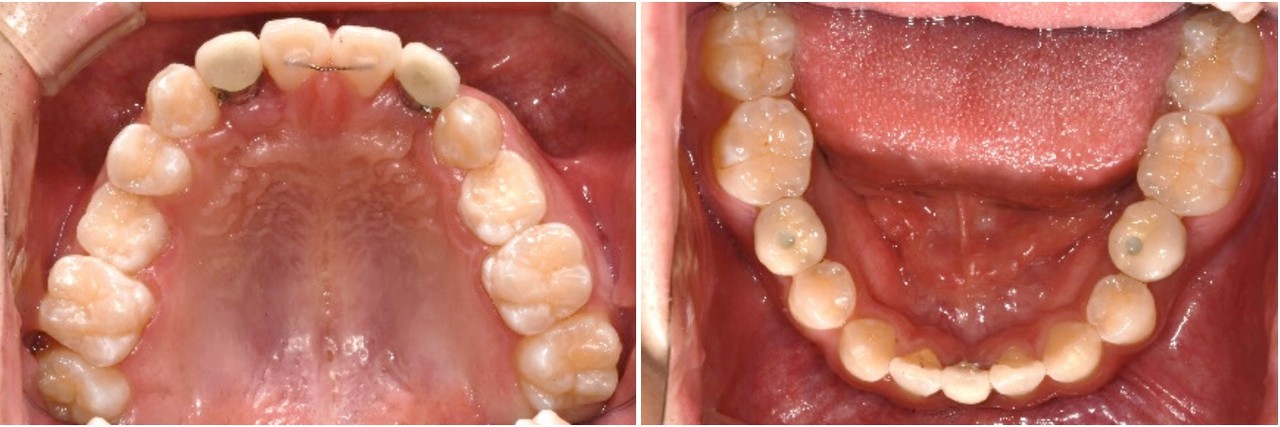

충분한 양의 측절치 공간 확보후 임플란트 식립및 보철로 치료를 마무리하였습니 다. 치근이동이 원활히됨으로 인해 임플란트 식립하기 충분한 공간이 확보되었으며 중절치의 전방이동으로 반대교합이 해소되었습니다.

부분교정은 고정원 문제의 해결여부에 따라 전체교정에 비해 쉬울 수도 혹은 더 어 려울 수도 있으므로 임플란트 공간 확보를 위한 교정치료시 이를 고려하는 것이 필수적이라 하겠습니다.

일반적인 상악 측절치의 경우 전후방적 공간은 평균 6.5미리로 적정 임플란트의 직 경은 3.5미리가 적절하지만 위 증례의 경우 7.5미리를 교정원장님께서 확보해 주셨기 때문에 사용한 임플란트의 직경은 4.0미리를 사용하였습니다.